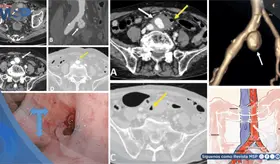

La paciente presentó cambios en el hábito intestinal y sangrado rectal con imágenes compatibles con lesiones estenosantes, inicialmente sospechosas de neoplasia sincrónica.

La trombosis de la vena espermática está asociada a enfermedades inflamatorias intestinales, como la colitis ulcerativa y la ileítis terminal, que generan un estado protrombótico debido a su naturaleza inflamatoria.

El estudio histológico confirmó un adenocarcinoma mucinoso de células en anillo de sello de vejiga con invasión muscular y diseminación metastásica pulmonar y ósea.

La pseudomelanosis vesical es una entidad extremadamente infrecuente, caracterizada por el depósito de pigmento de melanina en el urotelio y macrófagos de la lámina propia.